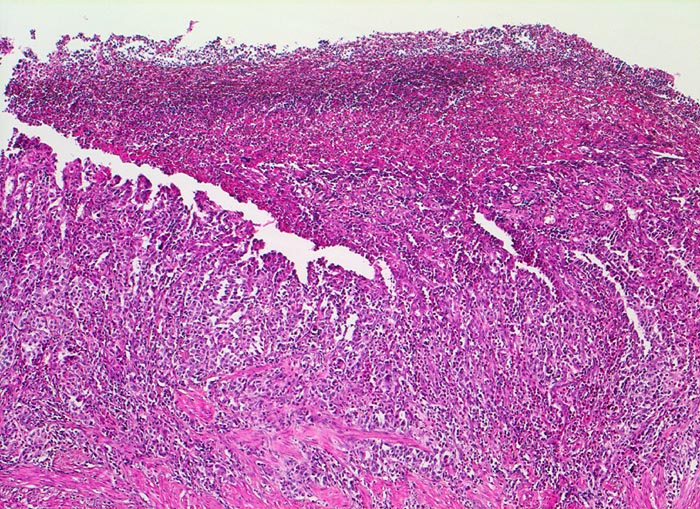

Magenfrühkarzinom

maligner Tumor

Magenantrum

Das Karzinom zeigt in diesem Abschnitt eine geringe Differenzierung. Eindeutige Drüsenbildung ist hier nicht sichtbar. Eine fibrinoleukozytäre Membran bedeckt den oberflächlich erodierten Tumor.

Endoskopische Kontrolle bei Patient mit bekannter chronischer Gastritis.

Histologie

50